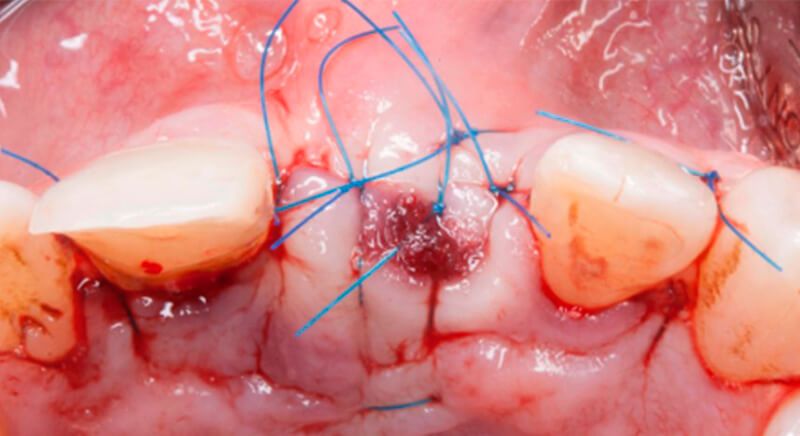

The guided surgery was performed by lifting a full thickness mucoperiosteal flap. A Biomimetic Ocean CC implant, diameter 3.5mm and length 10mm, was inserted using the surgical guide in the ideal three-dimensional position and the defects were regenerated with xenograft and reabsorbable membrane, the nasopalatine duct on the palatine side and the area of dehiscence on the vestibular.

During the same surgical intervention, a short 3mm Avinent healing abutment was positioned and fully covered by the flap. Primary closure was completed and we waited 6 months for the bone graft to mature.